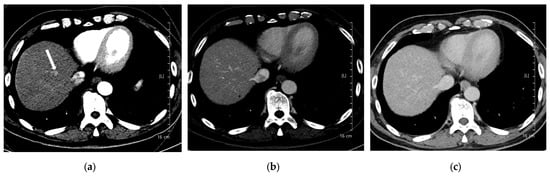

Figure 3. A 66-year-old man with hepatocellular carcinoma (HCC). CT was performed using high-concentration iodine contrast material (total iodine dose, 677.82 mg I/kg). Overall image quality in the arterial and portal phases was acceptable (mean scores more than 4): (a) A 15-mm enhancing nodule (arrow) is visible on the arterial phase at 120 kVp; (b) The nodule is inconspicuous on the portal phase; (c) Washout is evident on the delayed phase (arrow). Both reviewers diagnosed the lesion as HCC.